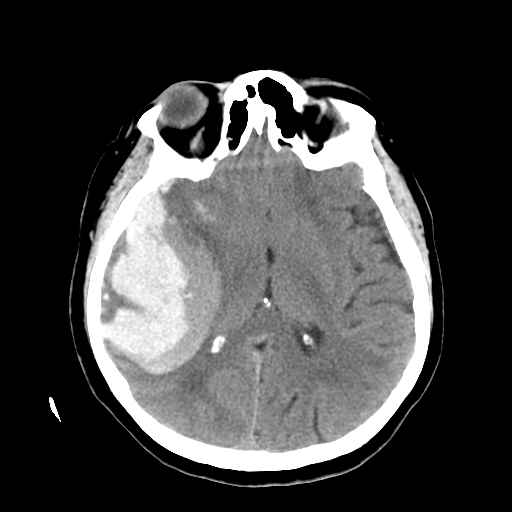

Sopra: aneurismi speculari della arteria cerebrale media (di cui uno a esordio emorragico - TAC con ematoma temporale)

La causa della formazione di queste dilatazioni (vedi i particolari di tre aneurismi, di cui due speculari della arteria cerebrale media e di cui il dx é responsabile della emorragia cerebrale visibile come una area bianca alla TAC) é talora ignota, altre volte legata a ipertensione, altre ancora associata a malattie diverse (rene policistico, sindrome di Marfan) che possono avere maggiore frequenza tra consanguinei.